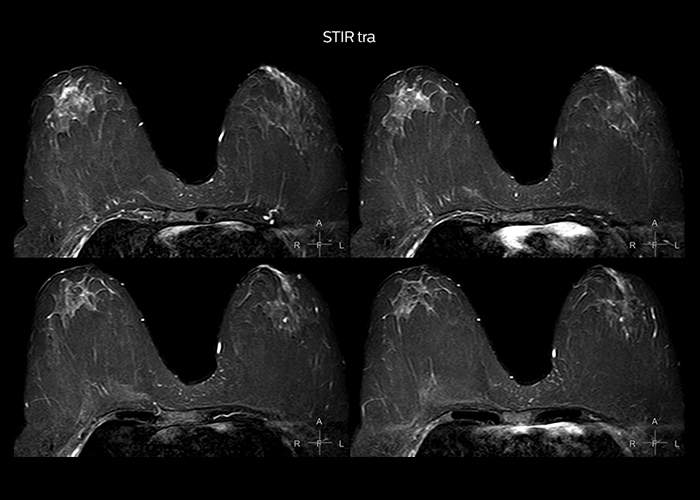

“To avoid coil changes we plan examinations of similar anatomies back to back, such as head and spine. Multiva helps us here a lot because coils don’t need to be changed frequently. Moreover, thanks to parallel imaging technology and 16-channel HeadSpineTorso and 8-channel MSK coils we are able to achieve excellent image quality. In this way Multiva helped us to increase both image quality and productivity.”

“Neurological cases, such as brain and spine imaging, represent the largest share in our MR scanning, followed by musculoskeletal cases. In general, we use simple and basic imaging protocols. But occasionally, we use advanced techniques for problematic cases if necessary.

“Most important, Multiva satisfies our clinical imaging needs very well,” says Mr. Tuna. “Many features of Multiva have become similar to the Ingenia system. Even in more complex imaging such as abdominal and cardiac, the image quality and performance of Multiva is better than we expected. General surgeons and physicians from our hospital’s internal medicine department prefer to refer to us because of this.”